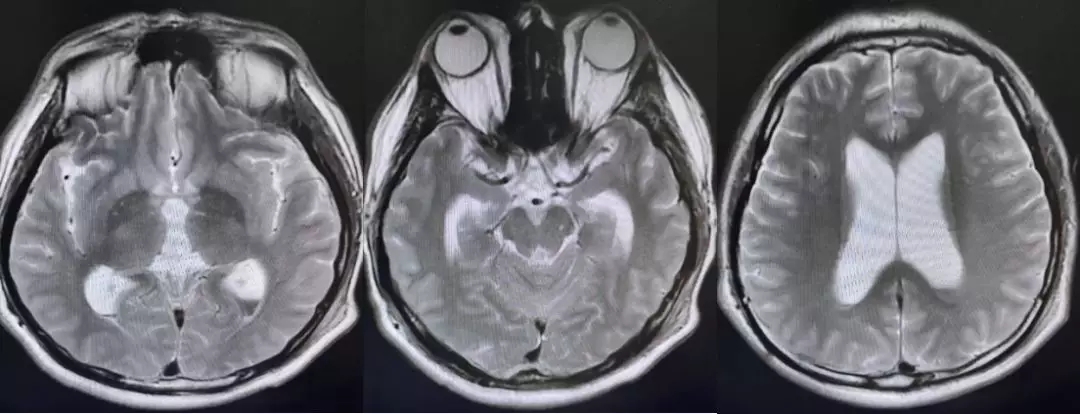

术后复查的核磁,肿瘤全切,未见残留征象。脑积水较术前改善。